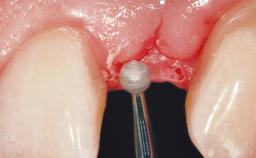

This 41-year-old female patient was referred to the clinic for the replacement of the right central incisor, since the tooth had developed a root fracture in the long axis that made extraction necessary. The healthy, non-smoking patient was first seen with the tooth still in place. A detailed Esthetic Risk Assessment was performed.The patient was worried about her dental esthetics and had high expectations for a successful treatment outcome from an esthetic point of view. The patient had a medium lip line that displayed parts of the gingiva in the anterior maxilla upon smile.